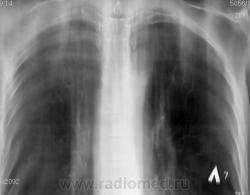

Для начала, неплохо бы R- граммы посмотреть, тогда будет понятна цель выполнения томографии.

По томограммам не понятно что хотели получить? Интересовали эти маленькие плотные очаги?

Справа на верхушке инфильтративная тень. Слева в задних отделах мелкие буллы.

На последнем срезе тень в 1 сегменте, мелкие полости в верхних долях с обеих сторон.